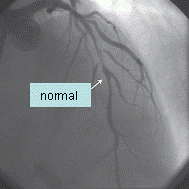

Figura 7. Coronarografie stanga a), dreapta b) stenoze multiple ateromatoase

Angiografia coronariana cu substanta de contrast efectuata la intervale de timp va arata gradul de evolutivitate al obstructiei coronariene si modul de dezvoltare a circulatiei colaterale (Dr. R. R. Mateescu, 2005).

Figura 8. angiografie coronariana: a) artera coronara normala; b) artera coronara cu ischemie.